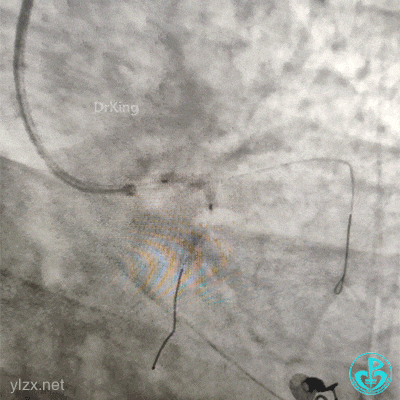

急诊造影

左冠脉造影发现左主干闭塞。

2.0×15mm球囊预扩张后。

植入4.0×13mm支架1枚。

交换导丝后扩支架网眼。

结束手术。